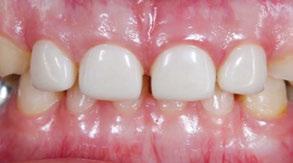

Several clinical solutions exist for primary anterior teeth with multisurface decay. Full coronal restoration of carious primary incisors may be indicated when caries is present on multiple surfaces, pulpal therapy is indicated, caries may be minor, but oral hygiene is very poor, or in a child with severe early childhood caries or a high caries risk diagnosis.1 Depending on the clinical scenario, a minimally invasive approach with the utilization of a high viscosity glass ionomer cement (HVGIC), with or without the combination of silver diamine fluoride (SDF) in a strip crown form, may pause the caries progression and provide an adequate clinical solution. Resin composite strip crowns have shown 80% retention rates and adequate parental satisfaction,1-4 although composite resin strip crowns have shown lower retention rates in teeth with decay involving three or more surfaces and particularly in children with a high caries risk4-6 (Figure 1). This could be from the continued high caries risk behaviors of the patient, as composite resin strip crowns in this population have shown to have increased inflamed marginal gingiva and gingival bleeding, increased plaque retention along the restoration, and loss of some restorative material.5,6

Figure 1: Occlusal films at recall visit in high caries risk patients showing loss of material and recurrent decay in composite resin strip crowns Figure